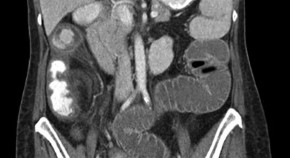

• A 33-year-old woman with a history of paroxysmal nocturnal hemoglobinuria (PNH) presented with abdominal pain, nausea and vomiting, accompanied by duodenal wall thickening seen on an abdominal CT scan and an ischemic-looking duodenal mucosa as visualized by endoscopy. She was diagnosed as having small bowel ischemia complicating PNH. Treatment with warfarin was started, but ischemic episodes recurred. Treatment with eculizumab was, therefore, proposed. This case highlights this rare gastrointestinal complication of PNH.